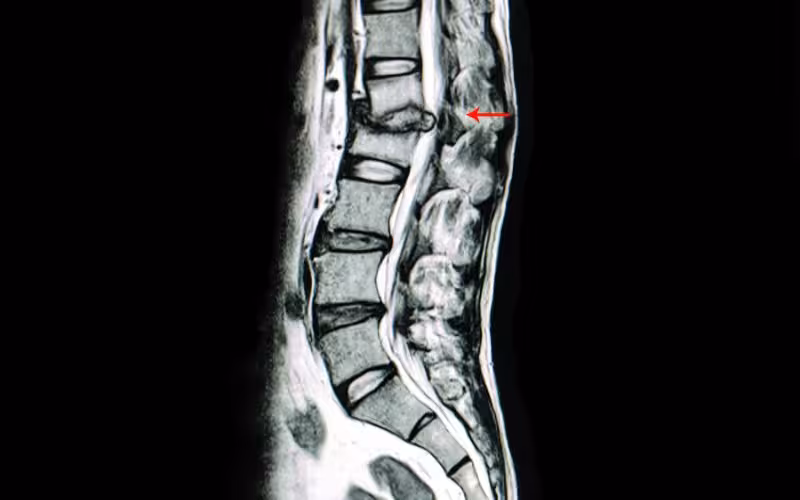

MRI scans (magnetic resonance imaging)

The big daddy of all imaging is the MRI scan. MRI provides better soft tissue contrast than CT and can differentiate between fat, water, muscle, and other soft tissue(CT is usually better at imaging bones).

The main benefit is that they do not use any form of radiation and are the imaging modality of choice when frequent imaging is required. However, MRI is more expensive than X-ray imaging or CT scanning. It is also poor at providing information about cortical bone.

The strong magnetic field created by the MRI scanner causes the atoms in your body to align in the same direction. Radio waves are then sent from the MRI machine, moving these atoms out of their original position. As the radio waves are turned off, the atoms return to their original position and send back radio signals. These signals are received by a computer and converted into an image of the part of the body being examined.

Suppose we want to look for a disc bulge, nerve root compression, bone stress injury or a detailed image of a soft tissue injury. In that case, we will use an MRI scan – but only under certain circumstances!